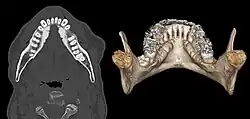

Torus mandibularis beidseits in der Computertomographie axial und dreidimensional rekonstruiert